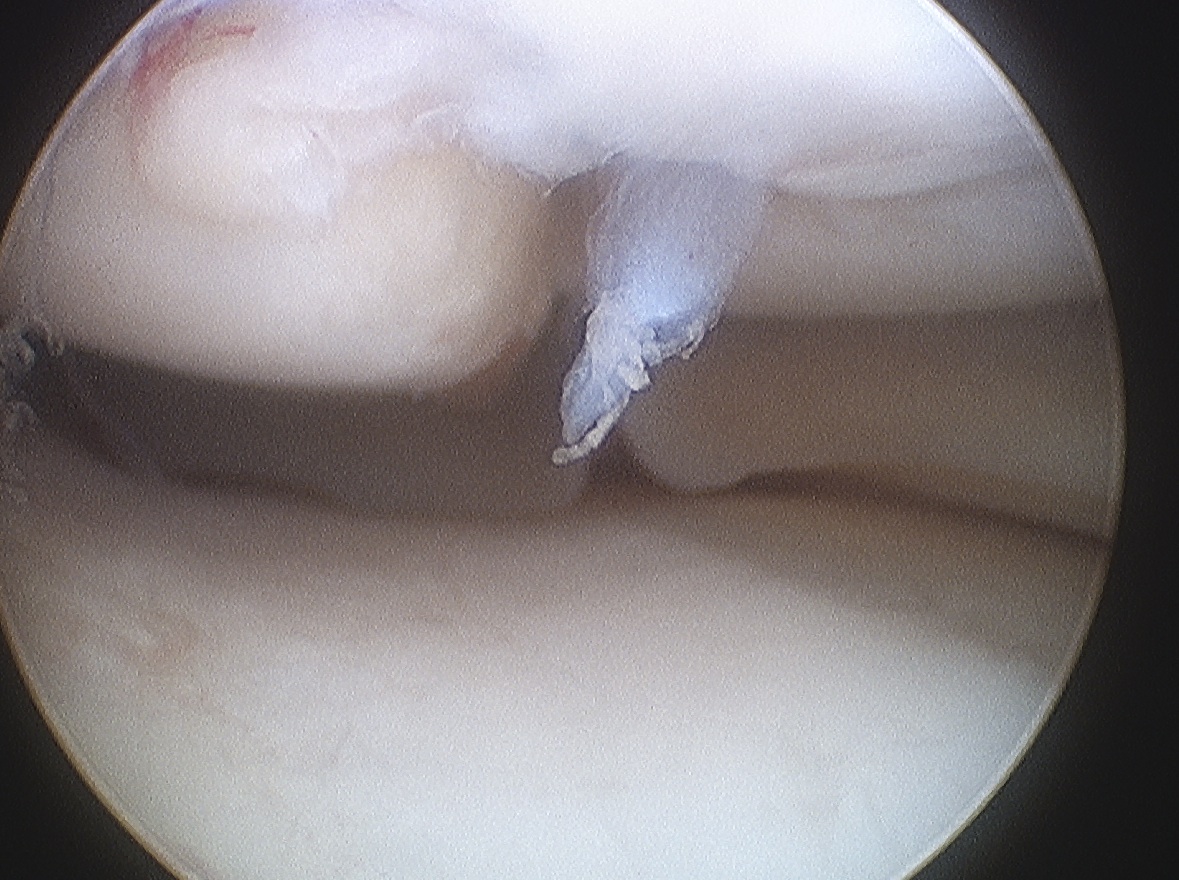

Minimally displaced loose body

Completely detached

ICRS Arthroscopic Classification

3. Completely detached but insitu

4. Fully detached with crater & loose body